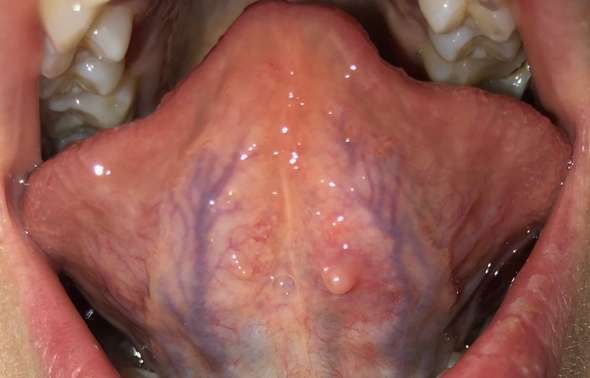

Fieberblasen oder Fieberbläschen können dazu führen dass schmerzhafte weiße Beulen unter Ihrer Zunge auf Ihren Lippen und auf der Innenseite Ihrer Wangen auftreten. Ein wichtiges Stomatitis-Virus ist das Herpes simplex Virus HSV 1 welches bei Kindern die Mundfäule Stomatitis aphtosa hervorruft. Herpes ist hochansteckend Aphthen dagegen nicht.

Beispiel für eine virale Ursache ist die sogenannte Herpes-simplex-Infektion. Sind Aphten wie Herpes. Die herpesartigen Blasen verbreiten sich vor allem auf der Innenseite der Lippe wachsen dort in großer Anzahl und schmerzen erheblich.

Herpes unterscheidet sich auch optisch von Aphthen. Manchmal entstehen Aphthen an der Zungenunterfläche oder am Zungenbändchen von kleinen Kindern wenn diese häufig mit herausgestreckter Zunge husten - so. Ein wohltuendes Mundwasser bei Zungenherpes können Sie selbst herstellen.

Blaschenhaufen Unter Der Zunge Was Ist Das Krankheit Mund Blaeschen